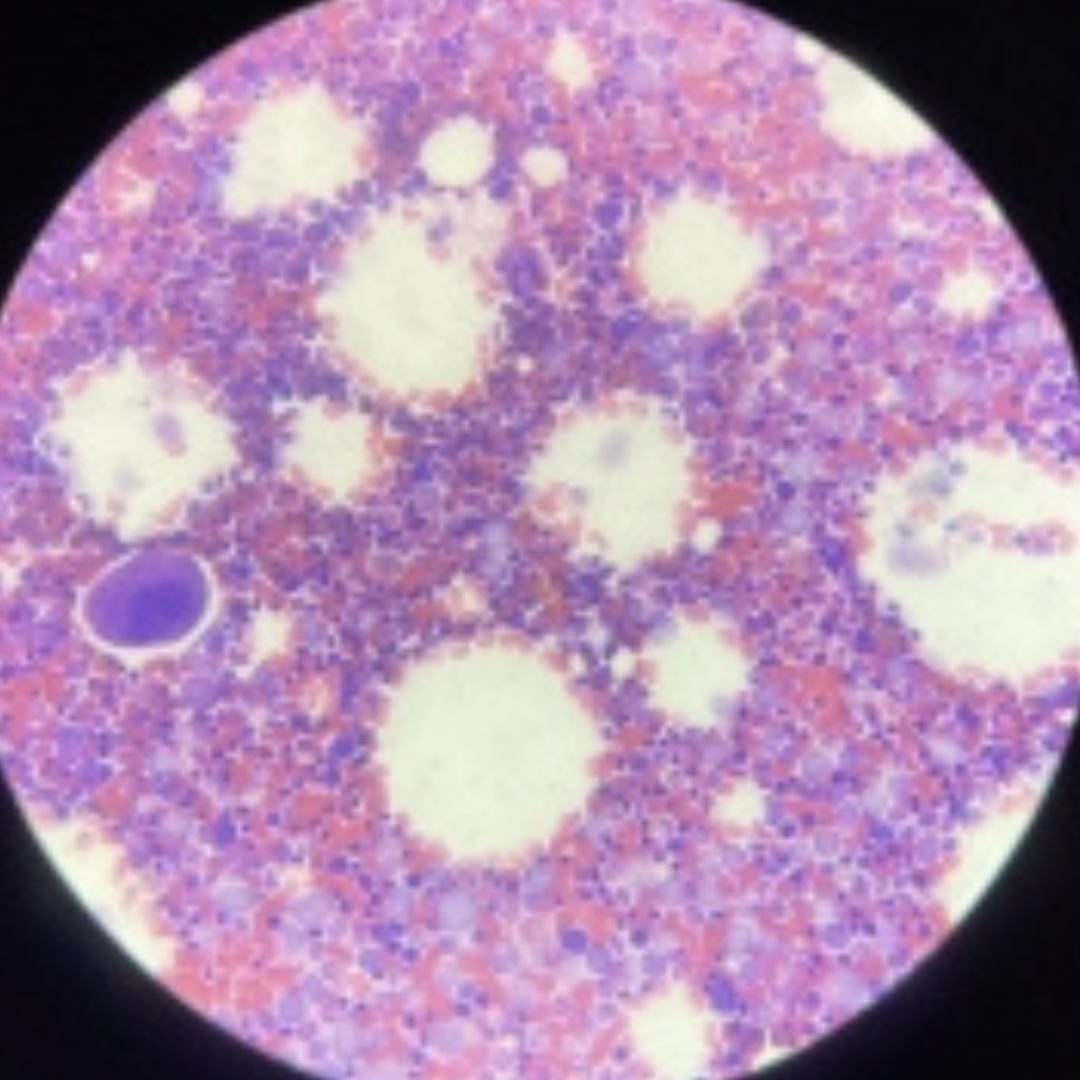

Bone Marrow

6

New cards

Bone Marrow

7

New cards

Bone Marrow

8

New cards

Bone Marrow

9

New cards

Bone Marrow